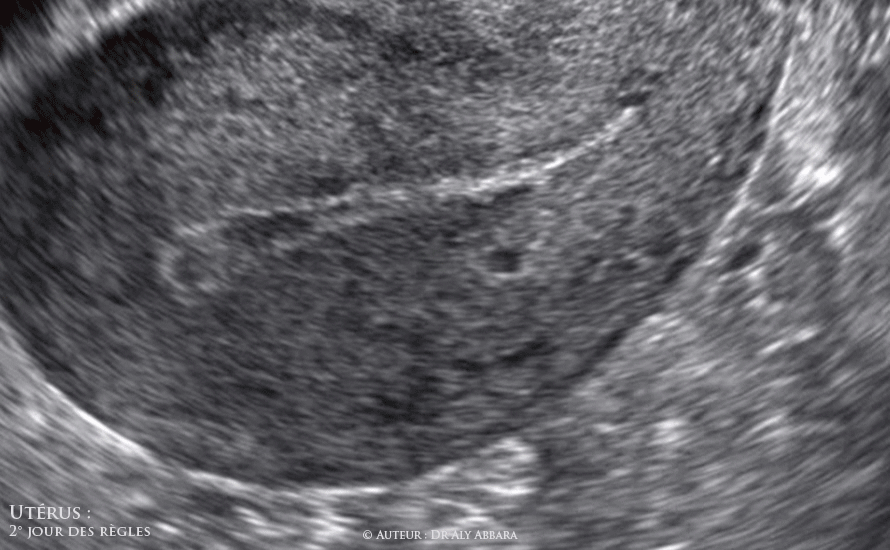

Échographie réalisée au 2e jour du cycle menstruel, on observe la présence des éléments suivants :

• 1- Le seul tissu endométrial restant est celui de la couche profonde qui se trouve en contact avec le myomètre, il s'agit de la fine couche basale, ou la couche endométriale génératrice. Cette couche subit très peu de modifications au cours du cycle menstruel, mais c'est elle qui générera, au cours du cycle menstruel, la couche superficielle (la couche déciduale = la couche qui tombera) de l'endomètre.

• 2- La cavité utérine est occupée, sur ces images, par le sang de la menstruation suite à la nécrose et la chute de la couche superficielle (déciduale) de l'endomètre ; ces phénomènes tissulaires endométriaux dégénératifs se reproduisent à la fin de la phase sécrétoire, en raison de la cessation des activités sécrétoires hormonales du corps jaune ovarien (hémorragie de privation hormonale).